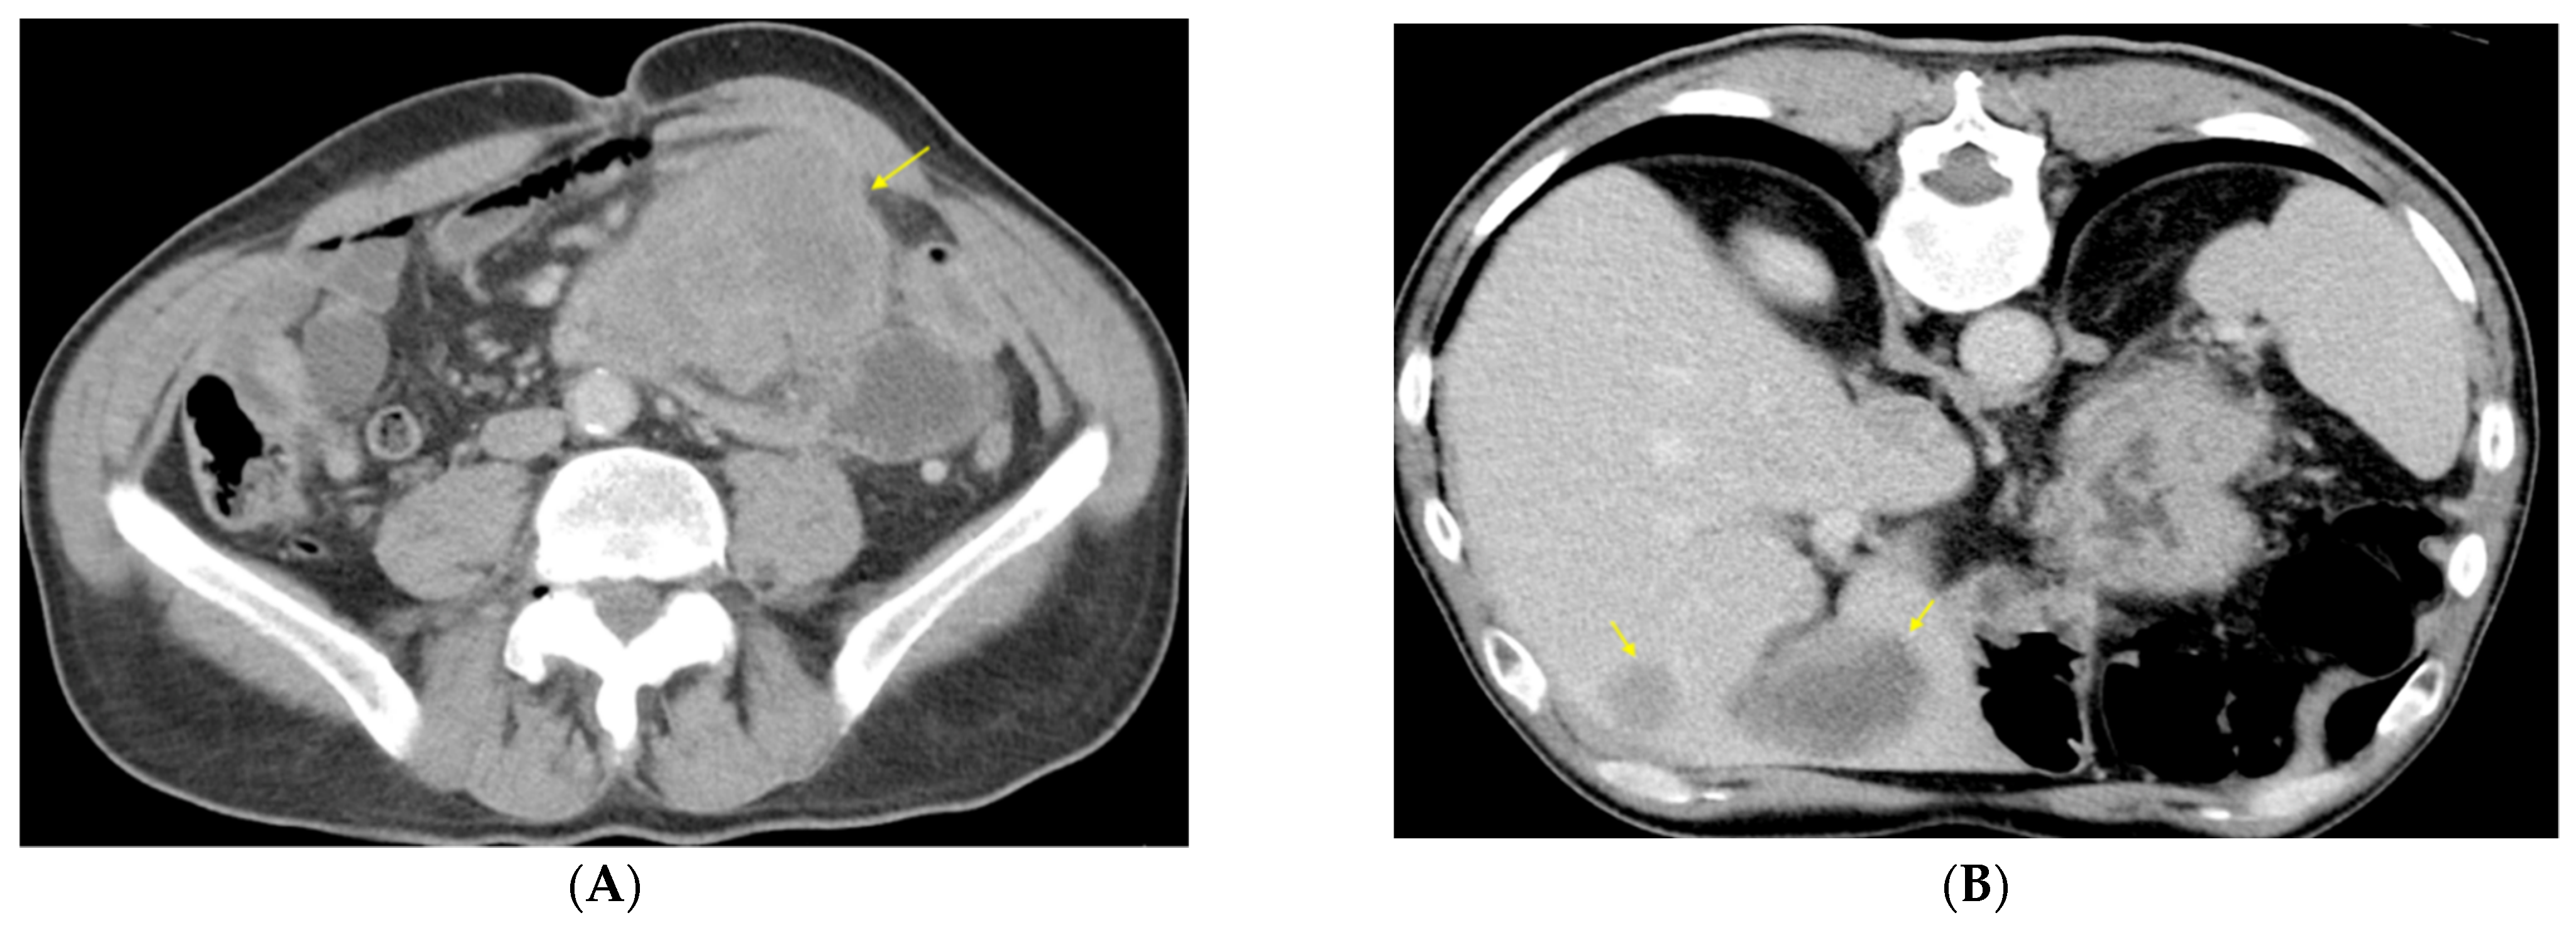

2. Case Presentation

Clinical Findings